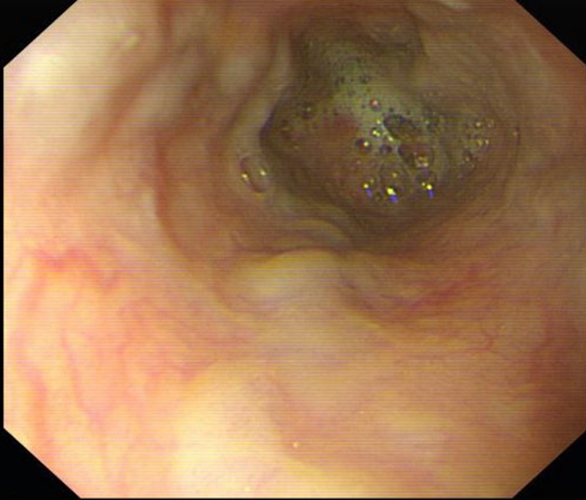

急性胃炎圖片

急性胃炎陽性表現

急性胃炎陽性的表現的

急性胃炎陽性的表現